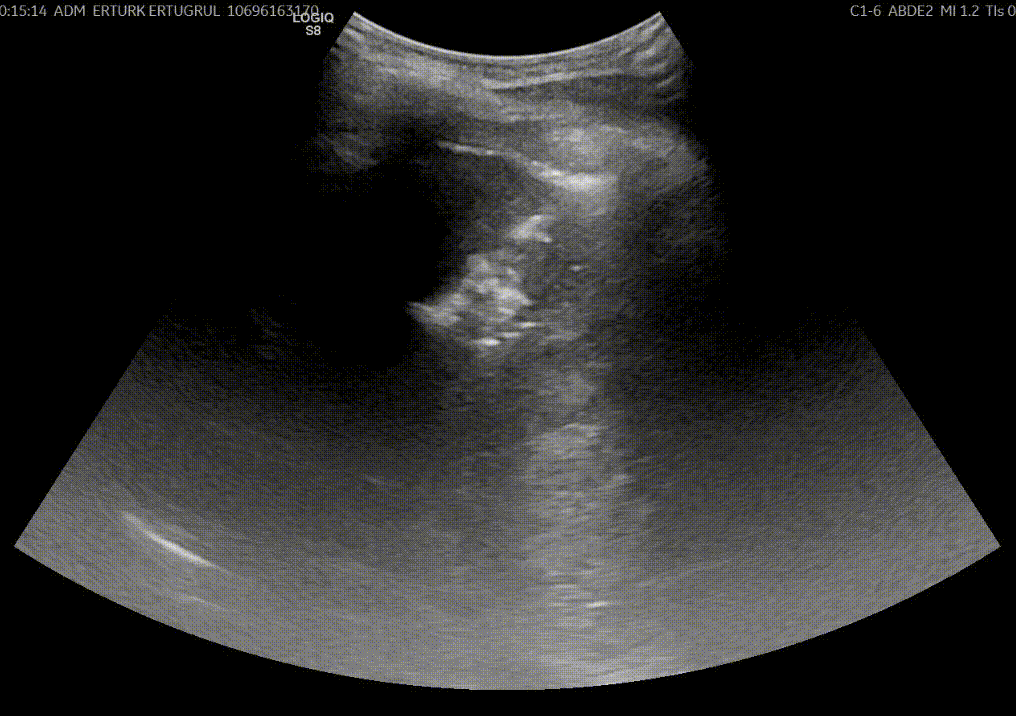

Girişimsel Onkoloji, kanser tedavisinde minimal invaziv yöntemleri kullanan, tıbbın hızla gelişen multidisipliner bir dalıdır. Bu yöntemler genellikle radyoloji ve görüntüleme teknikleri (ultrason, BT, MR, anjiyografi vb.) eşliğinde uygulanır.

- Radyofrekans Ablasyon (RFA): Kanserli dokunun yüksek frekanslı radyo dalgalarıyla yakılarak yok edilmesi.

- Mikrodalga Ablasyon (MWA): Mikrodalga enerjisiyle tümör dokusunun ısıtılarak ortadan kaldırılması.